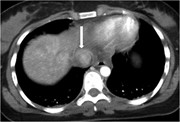

A rare opportunity for conservative treatment in a case of blunt trauma to the supradiaphragmatic inferior vena cava

Nicholas G. Matthees and others

Journal of Surgical Case Reports, Volume 2013, Issue 11, November 2013, rjt092, https://doi.org/10.1093/jscr/rjt092